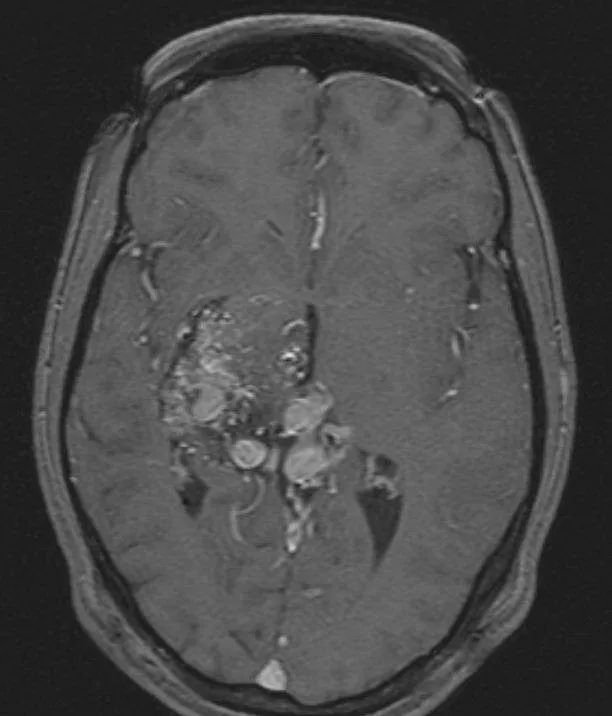

轴位T1加权像,既往行γ刀治疗

伽马刀治疗后

然而,就在伽马刀治疗 3 年后,造影显示AVM大部分闭塞,颞叶内侧少量残留畸形团向 BVR 引流。